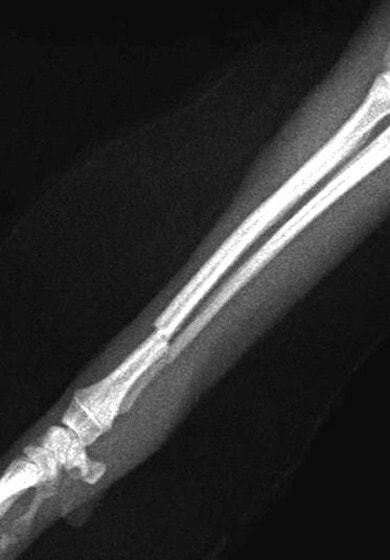

ペルシャ猫 11ヶ月齢 雄

他院にて左大腿骨遠位の成長板骨折(salter-harrisⅠ型)が認められており、治療相談を目的として来院。当院にて、キルシュナーワイヤーを用いたピンニングにより骨折部位の整復を行いました。術後の経過は良好で、現在も経過観察中です。

術前レントゲン